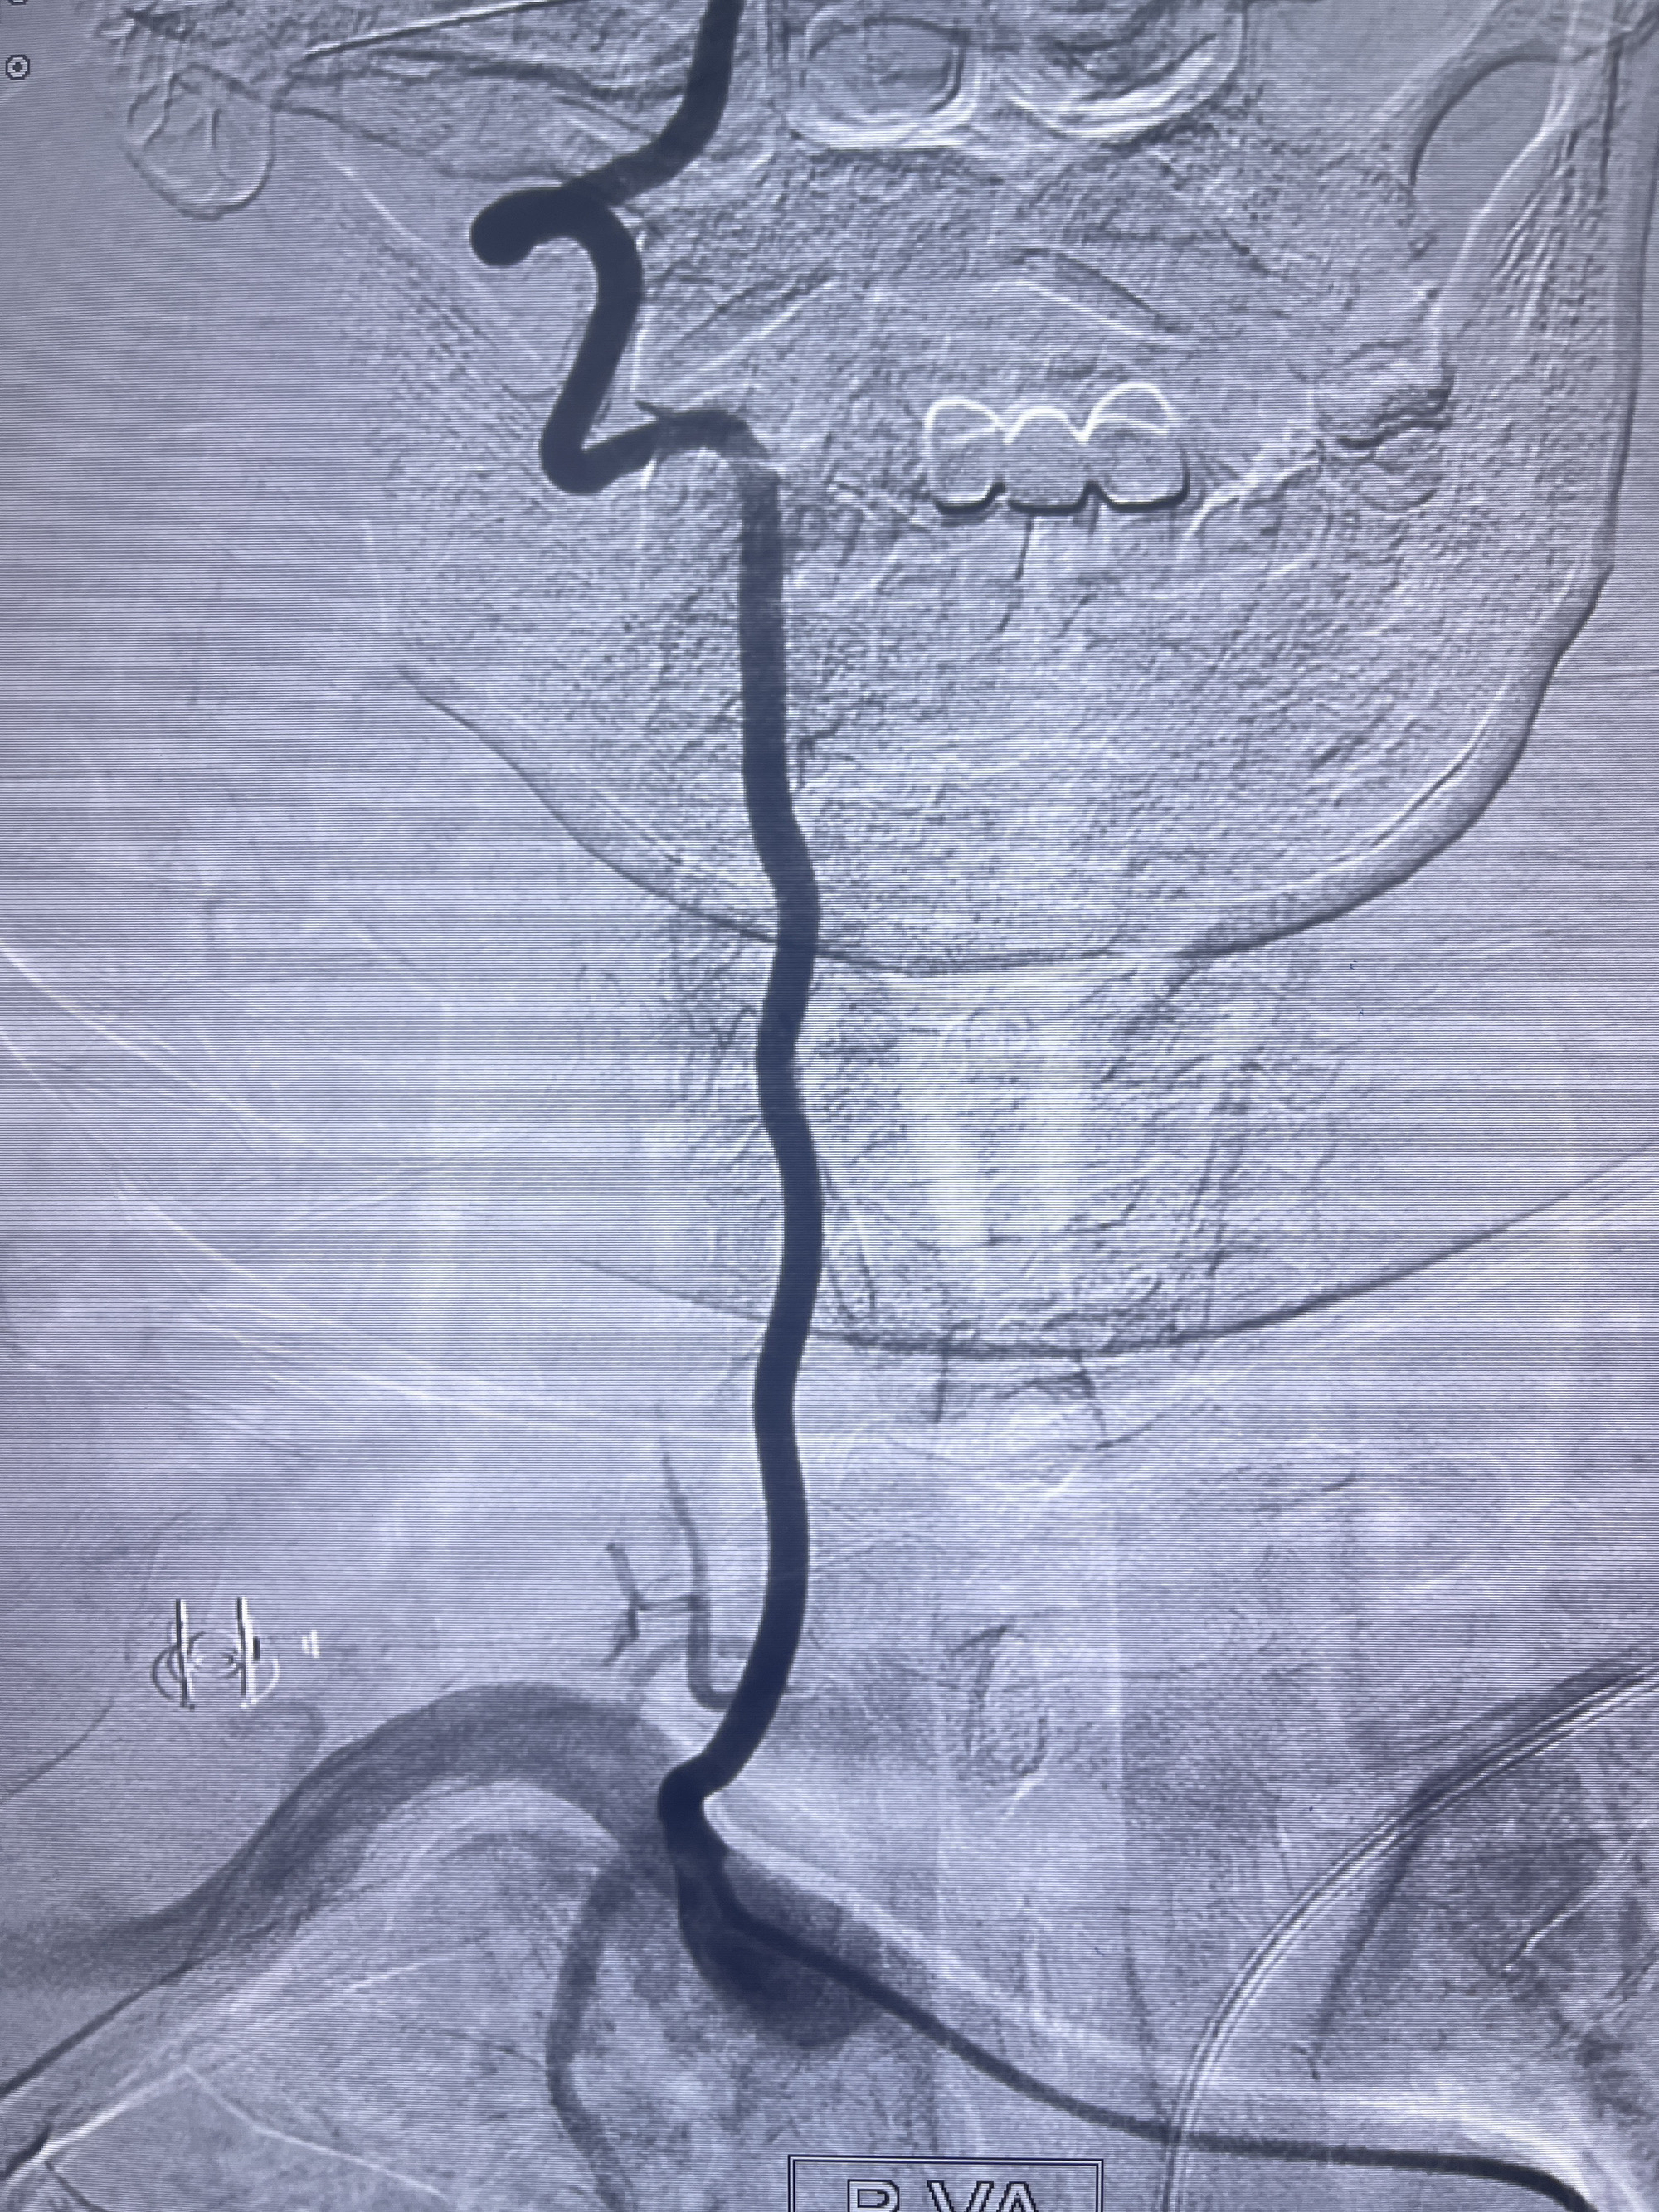

202.04.28脑血管造影:右侧大脑后动脉远段闭塞,右侧椎动脉V4段可见“囊状造影剂填充影”,大小7.64*7.65mm,可见PICA由动脉瘤发出;